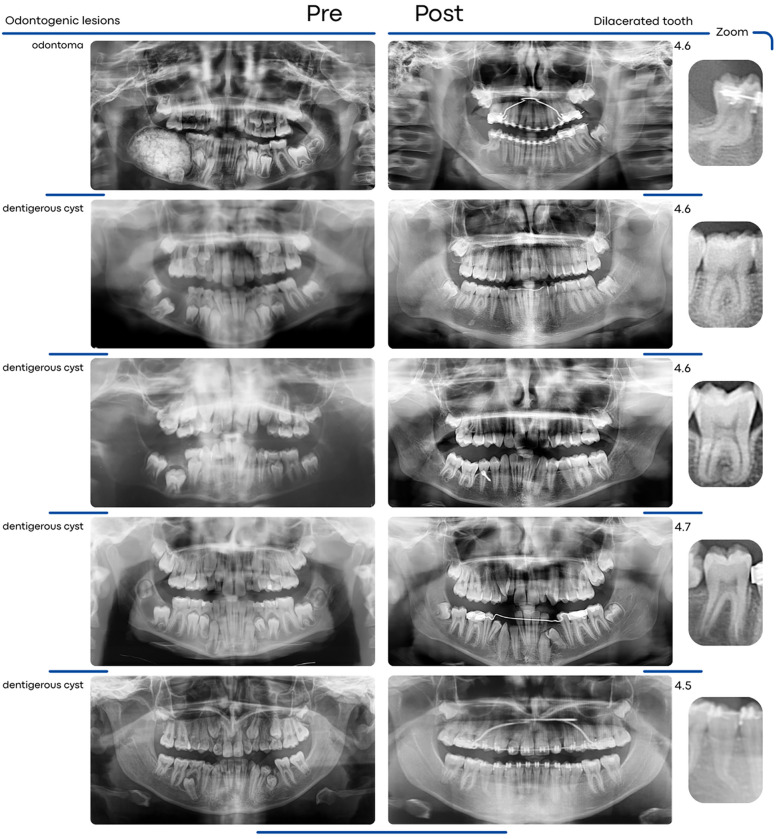

Methods: The sample size consisted of 22 impacted teeth divided into two groups: with odontogenic lesions (Group IwL) and without lesions (Group IwoL). Pre- and post-treatment radiographs, taken before and after conservative surgical or orthodontic-surgical management of impacted teeth, were used to assess the occurrence of dilaceration in both groups. Fisher's exact text was applied to compare the prevalence of dilaceration in both groups. In order to analyze the influence of each additional variable on dilaceration, a multivariate analysis was performed through logistic regression.

Results: Root dilaceration was significantly more common in Group IwL (72.73%) than in Group IwoL (18.18%) (p = 0.030). No significant association was found between root dilaceration and additional variables, including impaction depth, cortical bone contact, maximum lesion size, and lesion volume.